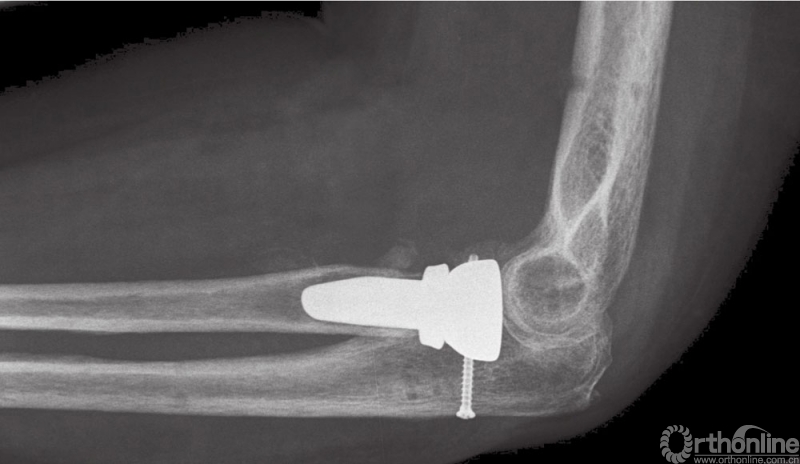

图9 (与图2为同一患者)使用铰链式外固定支架后的术后侧位X线片

图10 长期随访患者,正位片显示桡骨头假体位置满意,伴有少量异位骨化

图11 长期随访患者,侧位片显示关节复位满意